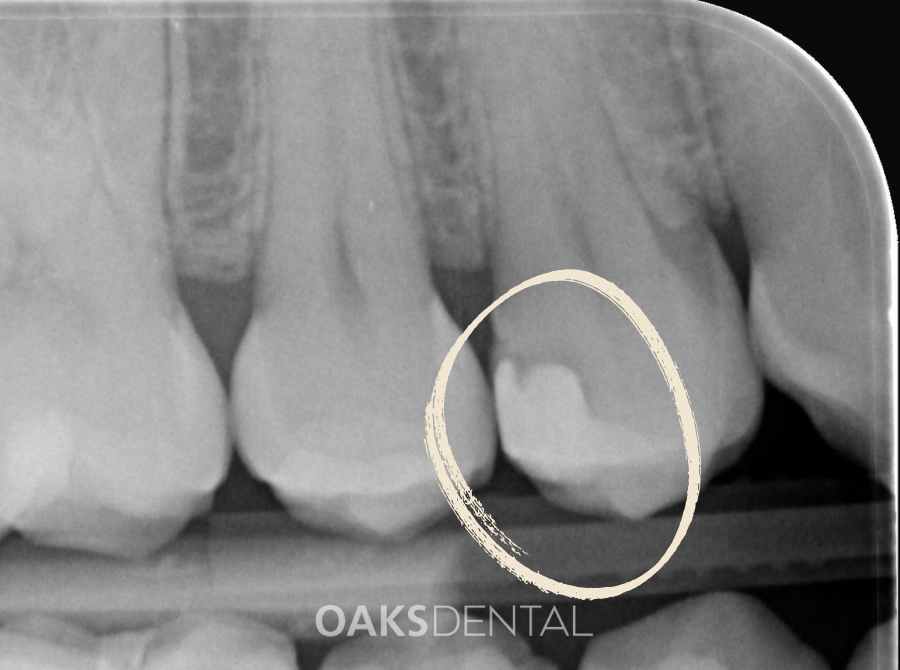

1. Examination & X-rays

We begin with a thorough assessment, including X-rays where needed, to determine the size and location of the decay or damage.

A dental examination and X-ray remain the most reliable ways to assess whether a filling is required.